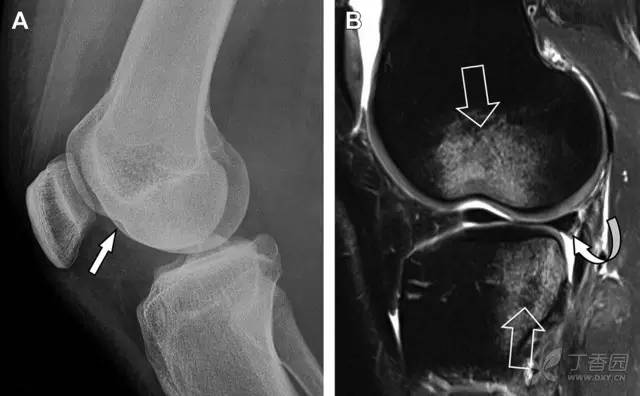

Segond 骨折是发生在胫骨平台外侧的垂直撕脱性骨折(图 4)。这种骨折在前后位 X 线片上显示最佳。

屈曲位时膝关节受到内旋*力暴**作用,导致皮质骨撕脱性骨折,这种骨折常发生在运动员身上。常引起股骨内髁和胫骨平台后内侧骨挫伤,75%~100% 的患者伴前交叉韧带断裂,33% 的患者伴外侧半月板损伤。

图 4 一位足球运动员的 Segond 骨折

A 正位片示关节线下方胫骨外侧皮质撕脱(箭头)。B MRI 冠状位 T1 加权像示附着于髂胫带的骨折碎片(空箭头)。